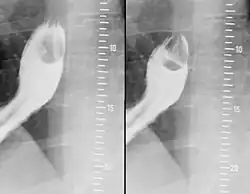

Makroskopisch handelt es sich um meist kleine, üblicherweise weniger als 3 cm messende, blass gelbliche, häufig unscharf begrenzte Tumoren von fester Konsistenz, die bevorzugt in der Zunge (40 %) sowie in Haut und Unterhaut insbesondere des Körperstammes (30 %) auftreten. Darüber hinaus wurden Granularzelltumoren an vielen weiteren Lokalisationen beschrieben, darunter Bronchialsystem (13 %), Harn- und Geschlechtsapparat (13 %), Magen-Darm-Trakt (6 %) oder Zentralnervensystem.[1][4][5]

- ↑ T. Schlick, T. Junginger: Abrikossoff-Granulosazelltumor: Ein seltener Tumor des Oesophagus. In: Chirurg. 1997 Sep;68(9), S. 932–935. PMID 9410685